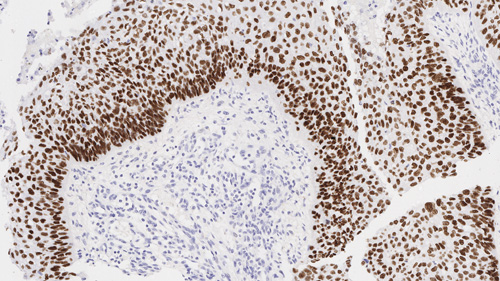

Squamous cell carcinoma of lung: Immunohistochemistry staining of p40. p40: clone BC28

p40 (Delta Np63) is a truncated product of p63. It is normally expressed in the basal or progenitor cell layer of stratified epithelia, basal cells of prostate, as well as myoepithelial cells of breast and salivary glands, and cytotrophoblasts in placenta, and shows a nuclear staining pattern with IHC. Among the numerous neoplasms positive for p40, squamous cell carcinomas of pulmonary and non-pulmonary origin can be identified from other malignancies.